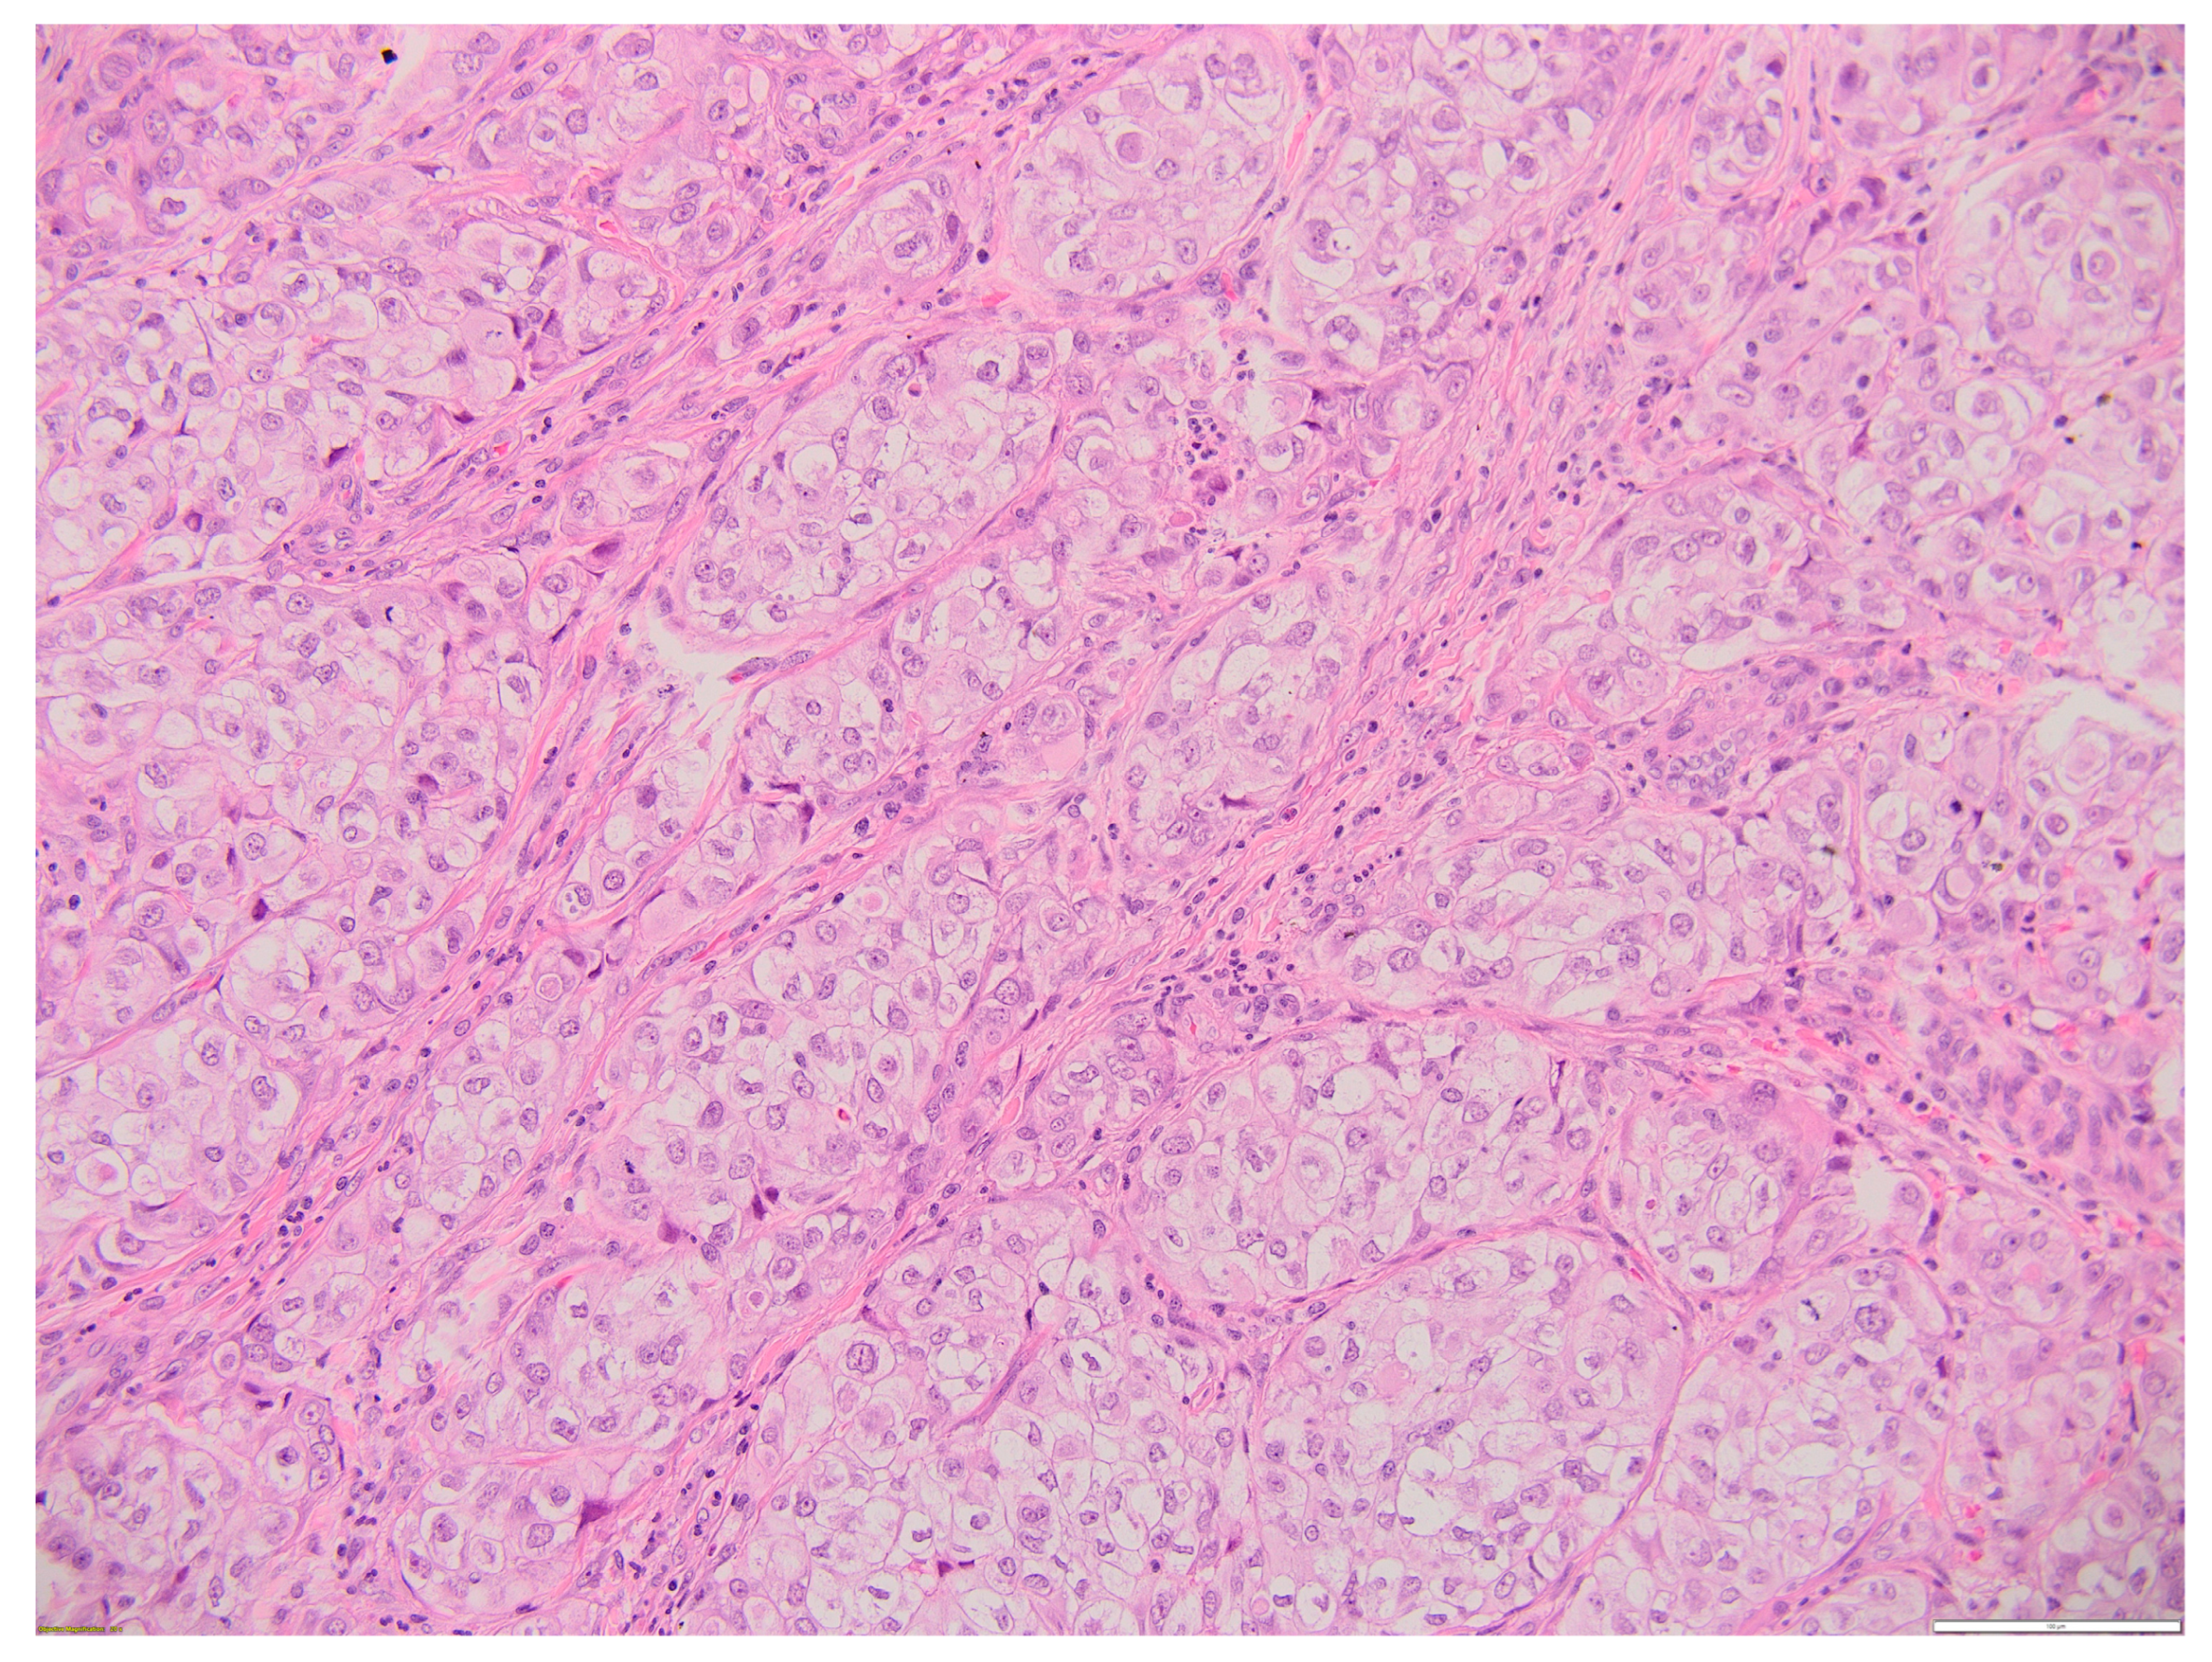

Aggressive Primary Thyroid Mucoepidermoid Carcinoma with Extensive Pulmonary Involvement

2. Case Report